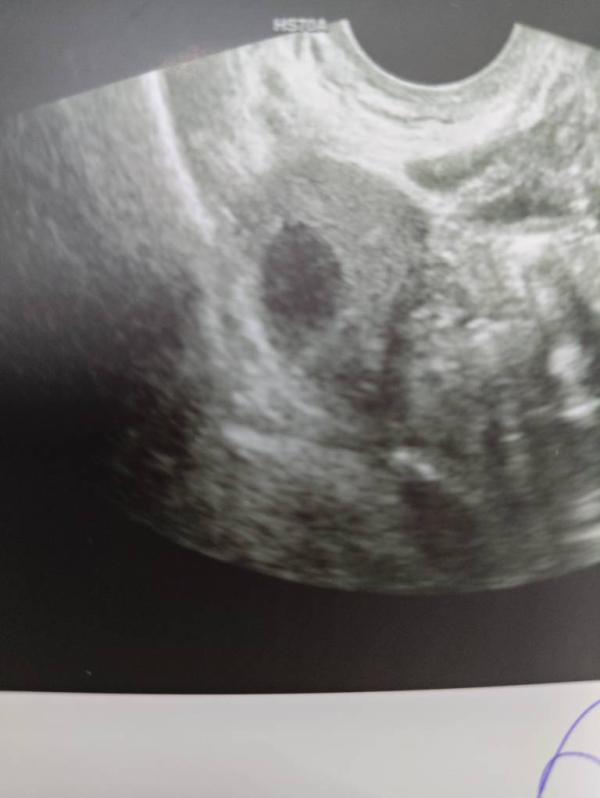

Девочки, может кто-то понимает в УЗИ. Врач не поняла, фолликул это или жёлтое тело. Мне поменяли врача перед УЗИ, на обычного акушера-гинеколога, и данную процедуру она проводит редко (по запросу)

По этому узи не совсем понятно. Обычно включают доплер, чтобы увидеть есть ли кровоток. Если кровоток есть, то это Желтое тело.

Доплер не включали( всё УЗИ длилось 2 минуты. Я спросила, что это, доктор сказала, что не понимает, может ДФ, а может и ЖТ. Овуляция была подтверждена УЗИ за 3 дня до этого

Вроде у желтого тела края у не такие ровные,